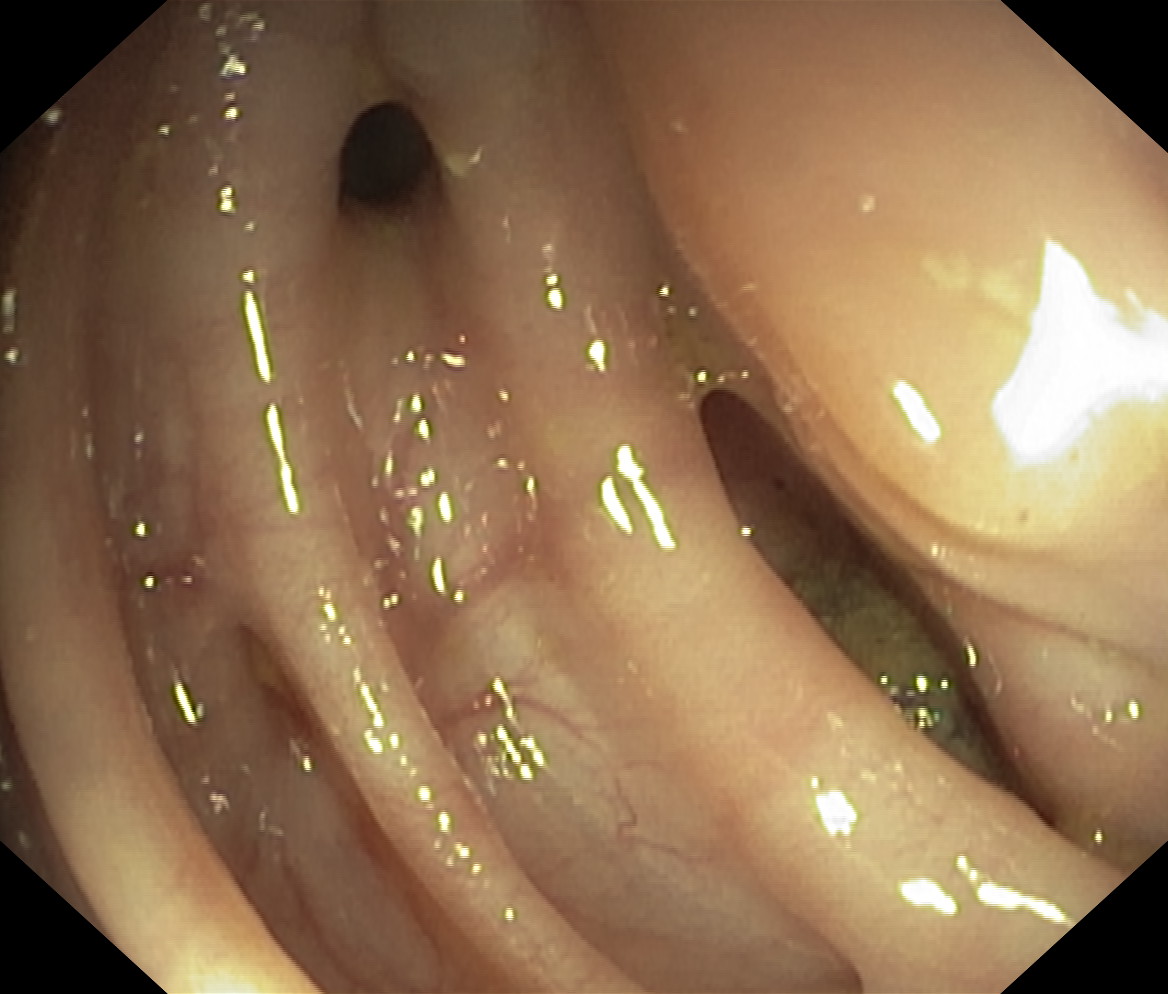

Uchyłki